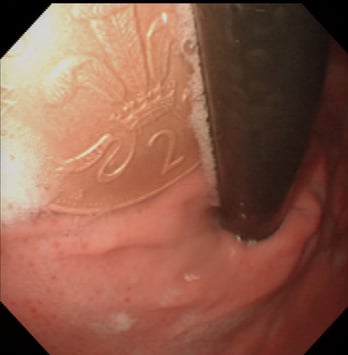

Oesophageal FBs are often the most challenging and can be true emergencies. There is a risk of perforation with pointed bones, and large objects such as indigestible chews can cause a complete obstruction (Figure 4A). Avoidance of surgical removal is preferred as it requires a thoracotomy, but surgery should be attempted sooner rather than later if endoscopic retrieval is unsuccessful. Because of the size of many oesophageal FBs, it is often easier to use long rigid alligator forceps alongside the flexible endoscope (Figure 4B). This allows visualisation of the procedure, but the endoscopist and the person manipulating the forceps must coordinate to avoid accidentally gripping the endoscope.